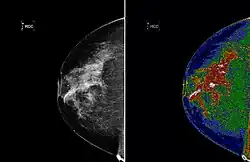

A region of interest (often abbreviated ROI) is a sample within a data set identified for a particular purpose.[1] The concept of a ROI is commonly used in many application areas. Existing as a vicinity, or within one. For example, in medical imaging, the boundaries of a tumor may be defined on an image or in a volume, for the purpose of measuring its size. The endocardial border may be defined on an image, perhaps during different phases of the cardiac cycle, for example, end-systole and end-diastole, for the purpose of assessing cardiac function. In geographical information systems (GIS), a ROI can be taken literally as a polygonal selection from a 2D map. In computer vision and optical character recognition, the ROI defines the borders of an object under consideration. In many applications, symbolic (textual) labels are added to a ROI, to describe its content in a compact manner. Within a ROI may lie individual points of interest (POIs).

Medical imaging

Medical imaging standards such as DICOM provide general and application-specific mechanisms to support various use-cases.

- Pixels (possibly non-contiguous) may be classified into segments encoded in a segmentation object as either binary or probabilistic values in a raster (which is not required to have the same spatial sampling or extent as the images from which the segmentation was derived); these are usually referenced by other objects containing structured content (structured reports)